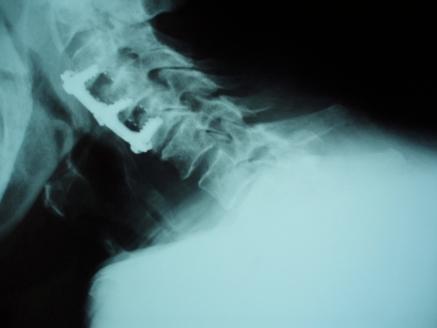

Dialysis-related spondyloarthropathy is a rare cause of spinal deformity and cervical myelopathy. Optimal management of cervical spine spondyloarthropathy often requires circumferential reconstructive surgery, because affected patients typically have both the anterior column and the facet joints compromised. The occasional presence of noncontiguous or "skip lesions" adds an additional level of complexity to surgical management, because decompression and fusion in an isolated segment of neural compression can worsen spine deformity by applying increased stress to adjacent cervical spine segments. We report two cases of hemodialysis patients who presented with cervical myelopathy and initially had anterior cervical discectomy or corpectomy. Because symptoms recurred due to hardware failure, both patients required posterior spine fusion as well. In retrospect, because of the hardware failure, both of these patients might have benefited from a circumferential (combined anterior and posterior) cervical spine reconstruction as their initial treatment.

透析相关性脊柱关节病是脊柱畸形和颈椎脊髓病的罕见病因。颈椎脊柱关节病的最佳治疗通常需要进行环形重建手术,因为受影响的患者通常前柱和小关节均受损。偶尔出现的非连续性或“跳跃性病变”增加了手术治疗的复杂性,因为在孤立的神经受压节段进行减压和融合会因对相邻颈椎节段施加更大压力而加重脊柱畸形。我们报告了两例血液透析患者,他们均表现为颈椎脊髓病,最初接受了颈椎前路椎间盘切除术或椎体次全切除术。由于内固定失败导致症状复发,两名患者均还需要进行后路脊柱融合术。回顾来看,由于内固定失败,这两名患者最初若接受环形(前后联合)颈椎重建术可能会受益。